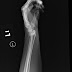

Distal Radius Fracture

Posted by Big Bad Wu since 2008 Christmas Eve at 8/25/2010 11:56:00 AM "The results of this study lead us to suggest that men over the ...